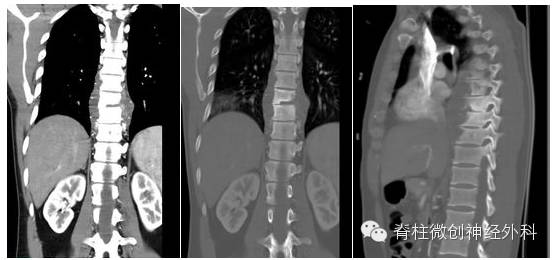

治疗后影像学检查资料:

影像学资料解读:脓肿大部吸收,但椎体塌陷造成轻度后凸

症状:虽然患者椎体塌出现后凸,但是患者症状未加重